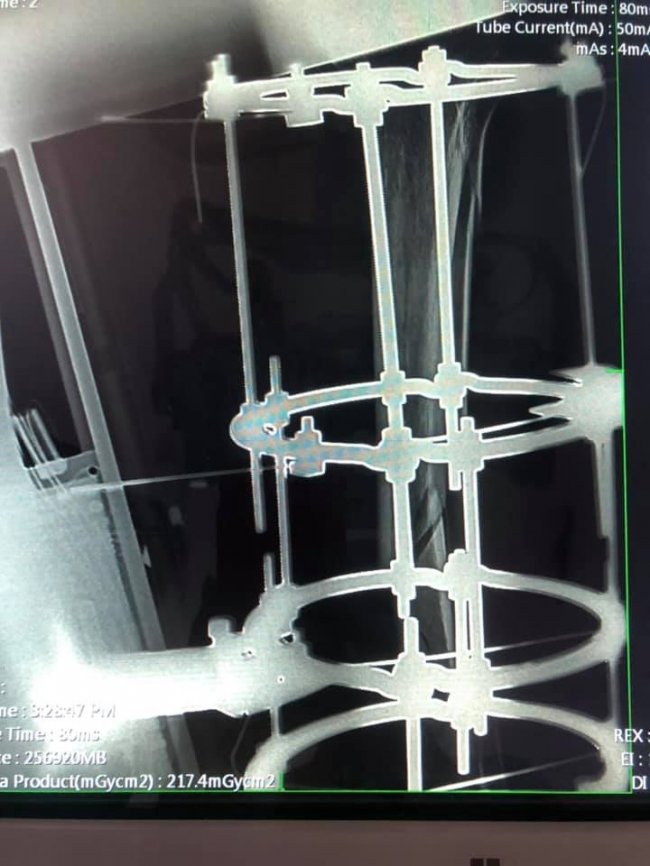

Після падіння з висоти чотирьох метрів у лікарню КНП "НЦМЛ" доставили 28-річного будівельника Петра. Після проведеного огляду та обстеження встановили діагноз: "Відкритий відламковий перелом обох кісток лівої гомілки в середній третині, зі зміщенням. Забійна рвана рана задньої поверхні лівої гомілки".

Після стабілізації фізіологічного стану хворого провели оперативне лікування, зокрема фіксацію перелому кісток лівої гомілки в апараті зовнішньої фіксації (АЗФ) Ілізарова. Цей метод лікування, за словами медиків, сприяє ранньому функціональному відновленню колінного та гомілково-ступного суглоба і мобільності рухів хворого при відкритому переломі.

Операція пройшла успішно. При проведенні рентгенологічного обстеження виявили, що фіксація відламків - задовільна.